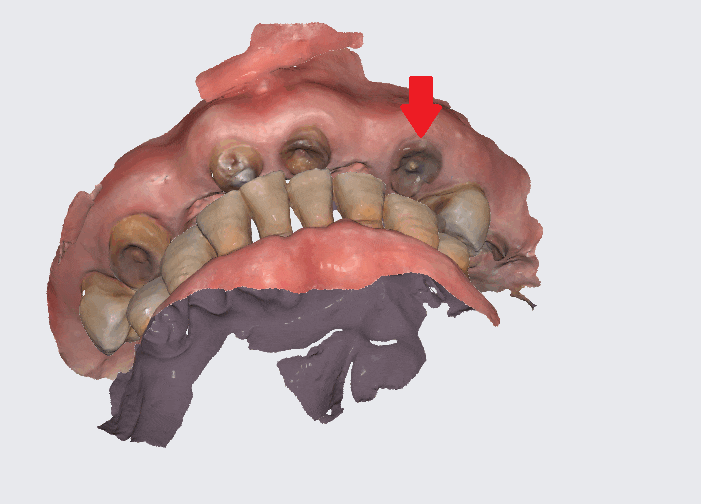

230817

스캐너의 경우

360도 요리조리 돌려보면서

어디 치아가 물리는지

확인이 가능하고

마모된 치아, 충치가 있는 치아까지

다 확인할 수가 있습니다.

재현도가 99% 비슷합니다.

거의 복붙수준이다 보니

위아래 전체 임플란트 환자분들의 경우

고덕역 치과에서 "디지털" 기계를 적극 활용할 수밖에 없습니다.